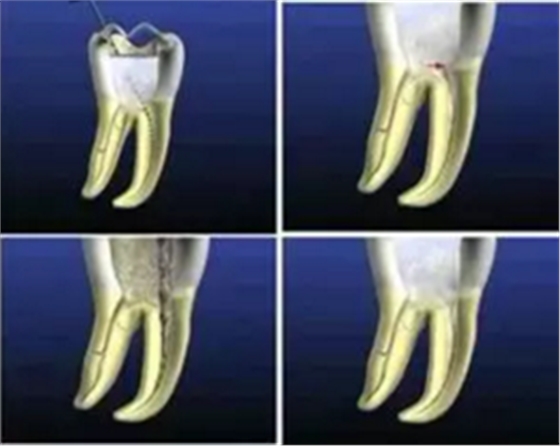

一、根管充填的步驟

2. 糊劑的導(dǎo)入

選好牙膠尖后開始根管充填,側(cè)方加壓術(shù)中可使用螺旋充填器導(dǎo)入糊劑。不要把螺旋充填器一直放在根尖狹窄部位置,避免糊劑超填,造成治療失敗。

螺旋充填器正確的使用步驟:螺旋充填器固定在距根尖孔 4-5mm 位置,進(jìn)行旋轉(zhuǎn)輸送。然后用牙膠尖或光環(huán) C 針做全長輕輕提拉,再使用螺旋充填器進(jìn)行輸送,保證根尖下端的填充。

3. 主牙膠尖的插入

主牙膠尖應(yīng)提拉插入,以避免超填。

主牙膠尖常選擇 02 錐度主牙膠尖,有下面幾個優(yōu)點(diǎn):

( 1 )能夠很好地到達(dá)根尖狹窄部。

( 2 )側(cè)方加壓時有較大空間,封閉型好。

4. 輔牙膠尖的插入

主牙膠尖插后選擇側(cè)方加壓器進(jìn)行側(cè)方加壓根管充填。

( 1 )側(cè)方加壓器的選擇:

術(shù)前應(yīng)選擇好,直徑為到達(dá)距根尖狹窄部2 -3mm 位置,避免將主牙膠尖擠壓出根尖狹窄部。

( 2 )操作:加壓時沖牙膠位置擠壓,拿出側(cè)方加壓器后立即插入輔牙膠尖。

金屬器械取出時牙膠尖有回彈,如果輔牙膠尖放置時間過長,不能到達(dá)側(cè)方加壓位置,可能造成中間空隙??稍谘滥z尖上蘸一些糊劑送入。關(guān)鍵是迅速插入輔牙膠尖。

5. 致密加壓

插入輔牙膠尖后,去除多余牙膠,使用垂直加壓器垂直致密加壓。

操作:進(jìn)行完根管充填、牙膠放好后,使用垂直加壓器,從根管口向根管方向垂直加壓,壓入 1-2mm 。

優(yōu)點(diǎn) :封閉冠,預(yù)防牙冠方的的細(xì)菌感染。

6. 術(shù)后 X 線片

術(shù)后 X 線片用來評定根管充填 長度、致密度(管壁清晰、側(cè)枝)等指標(biāo)。

圖為根管充填術(shù)后 X 線片。圖中可見,根管充填較好。右下圖有白色小點(diǎn),為側(cè)方加壓導(dǎo)致糊劑擠出所致,表明根管充填比較致密。

致密、恰到好處的充填可去除干凈根管里感染灶,機(jī)體逐漸恢復(fù)。